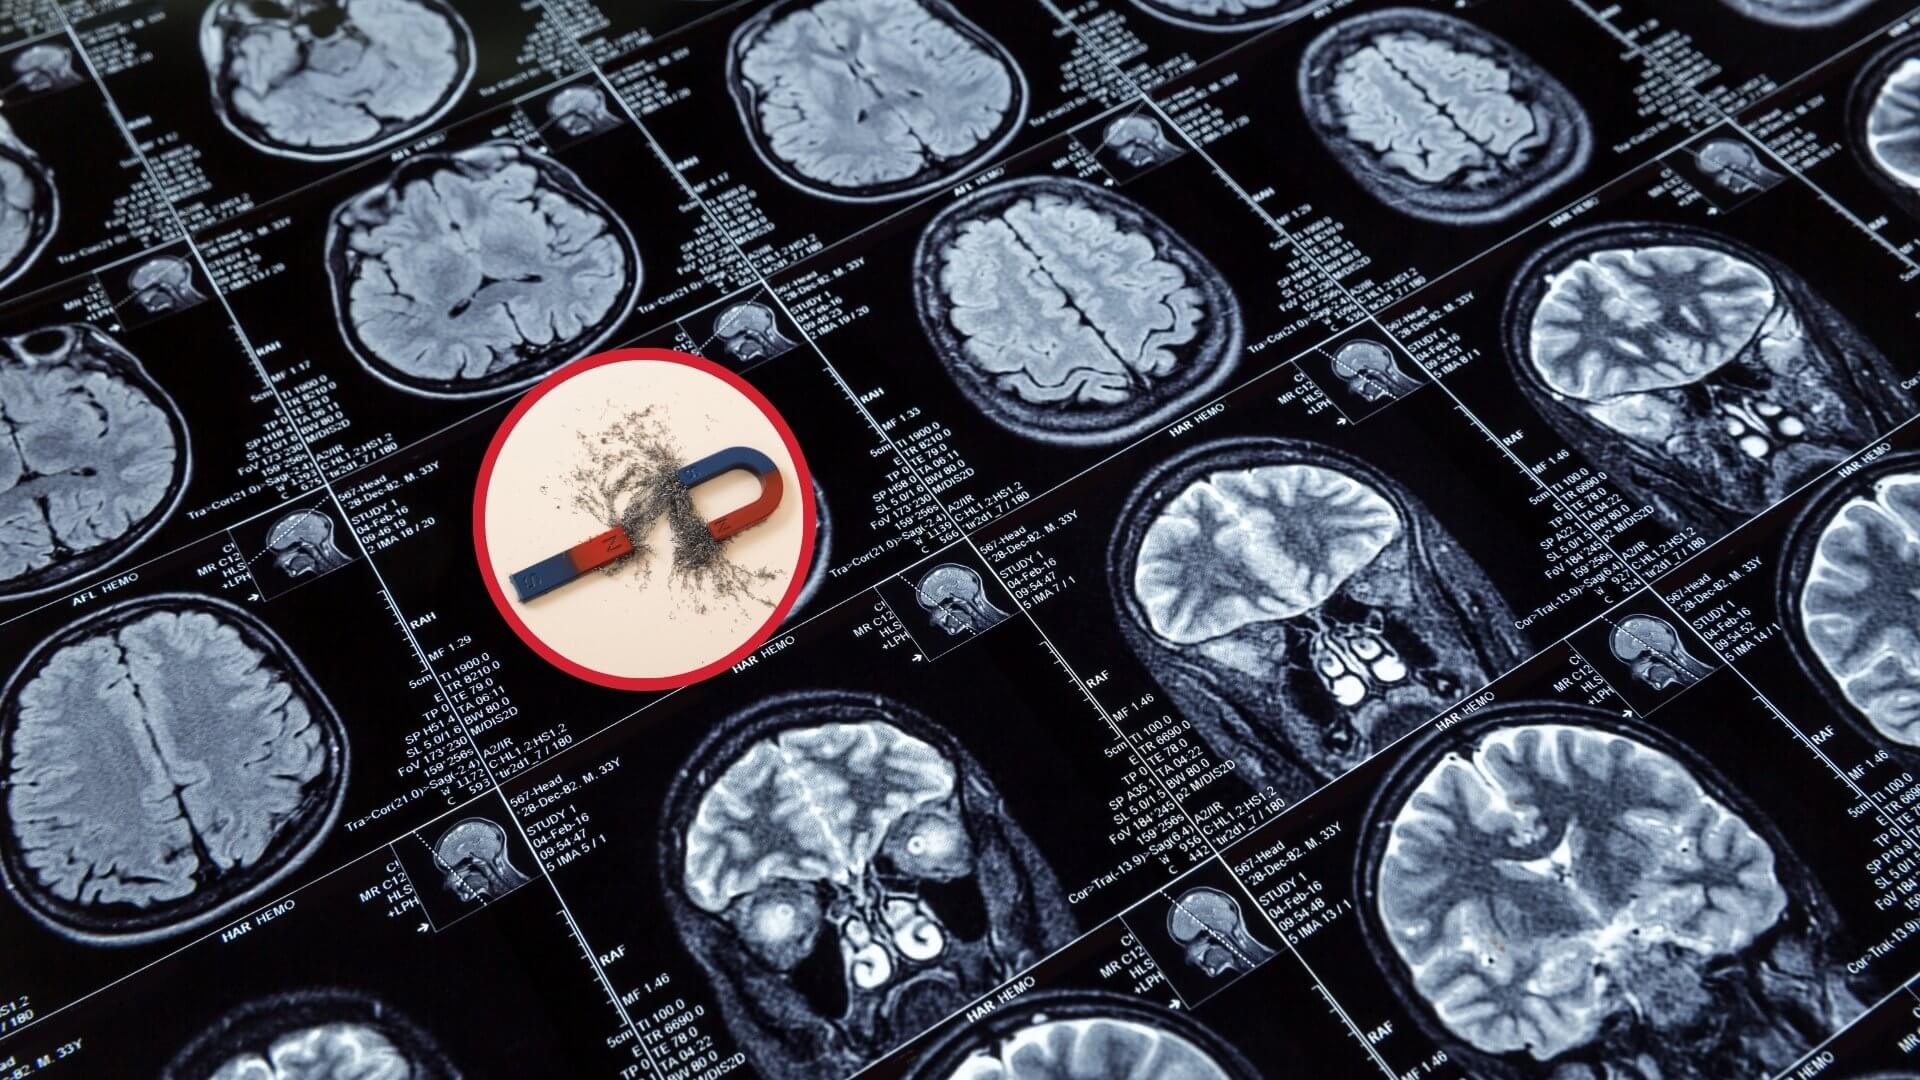

Estos campos magnéticos tan intensos son necesarios para vencer la agitación térmica existente a temperatura ambiente en los átomos y moléculas que constituyen los tejidos del paciente y de esta manera forzar a una gran cantidad de momentos magnéticos de núcleos de hidrógeno a alinearse en el sentido del campo magnético. De esta manera, serán muchos los núcleos de hidrógeno en el estado fundamental que podrán ser excitados mediante ondas de radiofrecuencia para desexcitarse luego volviendo al estado fundamental, emitiendo así en conjunto señales de radiofrecuencia de intensidad apreciable. Para producir campos magnéticos superiores a 1 Tesla se hace uso de bobinas o solenoides fabricado con hilo superconductor de niobio-titanio (la superconductividad es otra propiedad puramente cuántica), que requieren ser mantenidos a una temperatura de 4 Kelvin en una cámara criogénica interna que contiene helio líquido, la cual a su vez se halla en el interior de otra cámara criogénica externa que contiene nitrógeno líquido a una temperatura de 77 Kelvin.

En los sistemas actuales, el helio líquido solo necesita ser repuesto cada dos o tres años. La elevada intensidad de estos campos magnéticos puede ocasionar accidentes si de forma descuidada objetos ferromagnéticos son introducidos en la sala en la que opera el escáner debido a que al ser atraídos por el imán pueden salir disparados hacia él. En los escáneres de RMN en los que el tubo se sustituye por una forma abierta en U para evitar la claustrofobia, el campo magnético se obtiene mediante imanes permanentes de tierras raras y es más débil que el producido por el solenoide superconductor. Por esto último, en estos escáneres abiertos la razón señal-ruido de la imagen, y por tanto su calidad, es menor.

A estos campos magnéticos estáticos del orden del Tesla y extremadamente homogéneos (con una variación espacial de unas pocas decenas de partes por millón) se le superponen en el escáner campos magnéticos estáticos más débiles de decenas de militeslas, apuntando en la misma dirección y sentido. Estos campos magnéticos más débiles varían linealmente con la distancia y se generan con unas bobinas convencionales, no superconductoras, que se denominan bobinas de gradiente. Las bobinas de gradiente son las responsables del ruido elevado que puede incomodar al paciente durante la exploración y se debe a las vibraciones ocasionadas por las fuerzas magnéticas que actúan sobre las corrientes en dichas bobinas. La superposición del campo magnético intenso y homogéneo del solenoide superconductor con los campos magnéticos más débiles producidos por las bobinas de gradiente y que varían linealmente, da lugar a un campo magnético estático total muy intenso que varía ligeramente de forma lineal con la distancia en las tres direcciones del espacio, X, Y, Z, aunque sigue apuntando en una única dirección, esto es, a lo largo del eje de la camilla del escáner o eje longitudinal Z, dirigido de los pies a la cabeza del paciente. Dado que la frecuencia de Larmor con que precesionan los momentos magnéticos es proporcional al valor del campo magnético, el resultado es que los momentos magnéticos de los núcleos de hidrógeno en los tejidos pueden precesionar con una frecuencia distinta dependiendo de la posición espacial que ocupan.